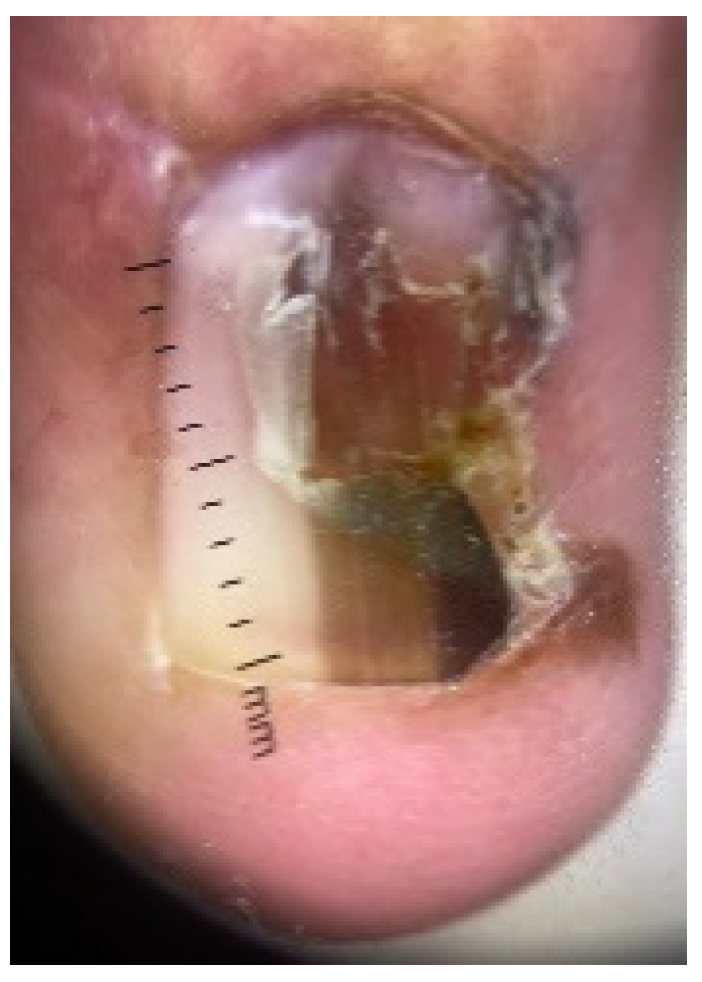

4.4. Acral Lentiginous Melanoma